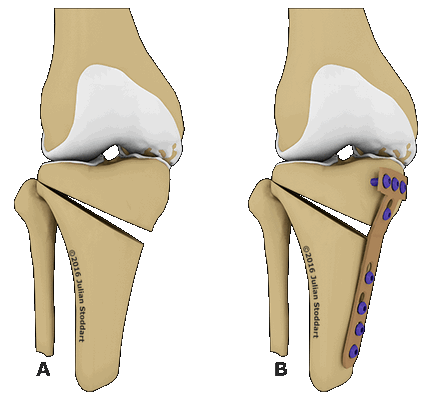

Схематичное изображение проведения операции.

Корригирующая остеотомия коленного сустава — операция, устраняющая врожденные и приобретенные костные деформации. Во время хирургического вмешательства врач иссекает заранее обозначенный участок костной ткани и соединяет свободные фрагменты костей имплантатами. В результате ось механической нагрузки переносится на здоровый участок сустава. Операция проводится под полной или спинальной анестезией. После лечения ортопед фиксирует нижнюю конечность пациента гипсовой повязкой на время восстановления. Проводится реабилитация.

Остеотомия с металлоконструкцией.

Остеотомия коленного сустава: визуальное изображение процедуры.

Костная ткань удаляется с помощью остеотома. Для предотвращения повреждения сосудов и нервов, проходящих через коленный сустав, коррекция проводится под контролем флуороскопа или рентгеновского аппарата. После пластики кожный покров сшивается, и нижняя конечность фиксируется гипсовой повязкой или шиной.

Не существует единого метода оперативного вмешательства, подходящего при любых показаниях. При выборе хирургической техники врач учитывает запланированный угол коррекции. Методы визуализации помогают точнее восстанавливать ось нижней конечности. В современной ортопедии чаще всего проводится открытая клиновидная остеотомия большеберцовой кости выше уровня бугристости.